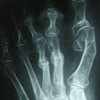

RESULTADOS

Caso 1: Hallux Valgus del Adulto